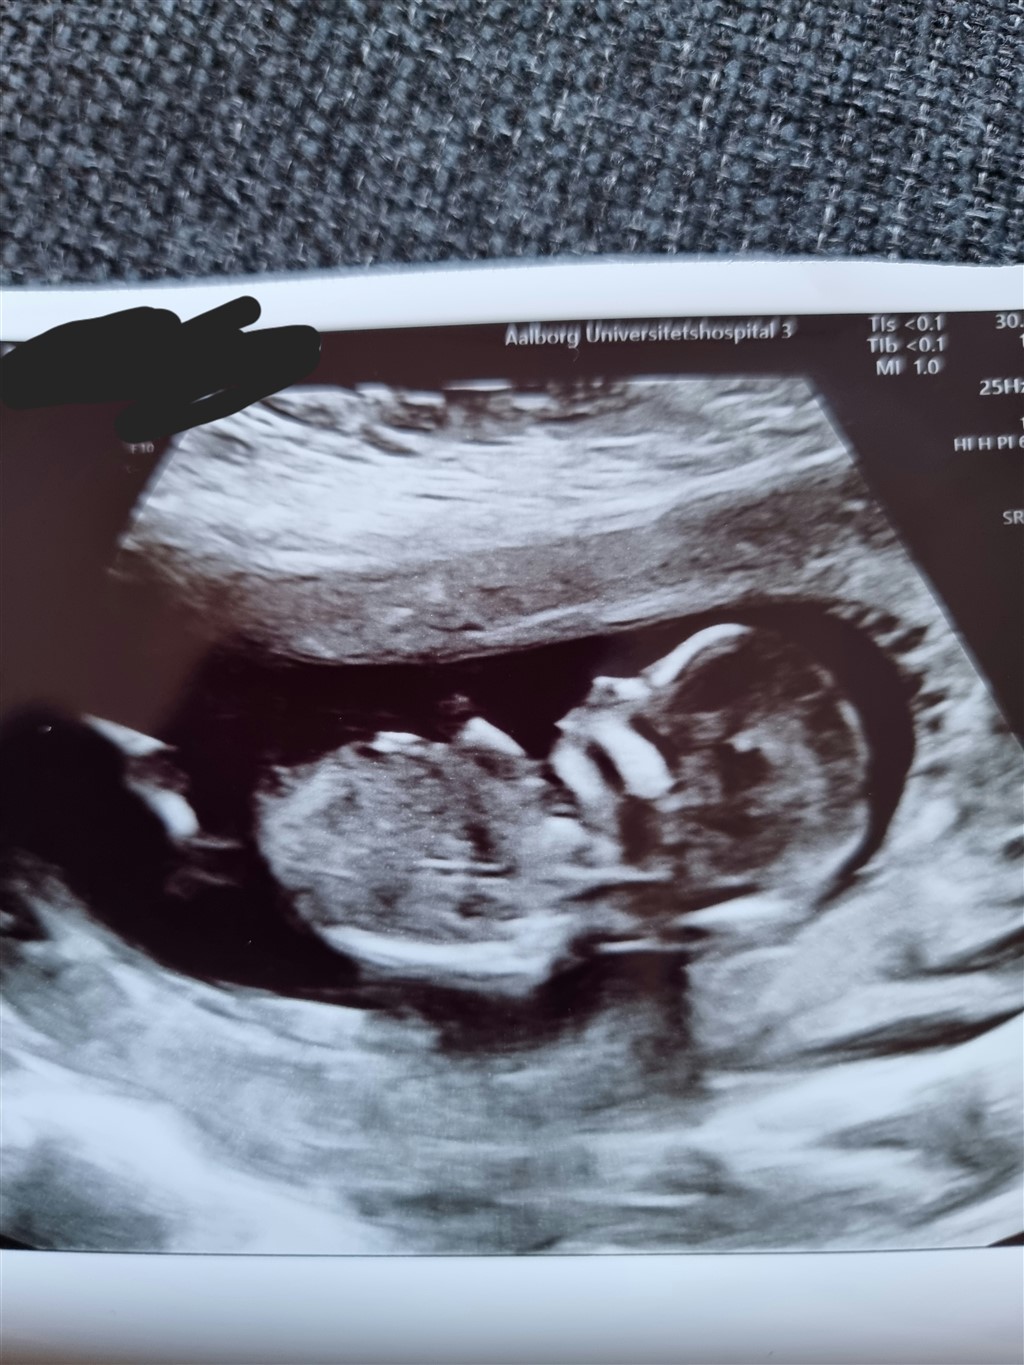

Kan nogen se om dette skulle være en dreng eller en pige? Er 13+6 på billederne.

Vedhæftede fotos (klik for at se i fuld størrelse)

Vil forsigtigt gætte pige

Jeg vil også sige pige ud fra skull theory, syne/ nub er svær at se.